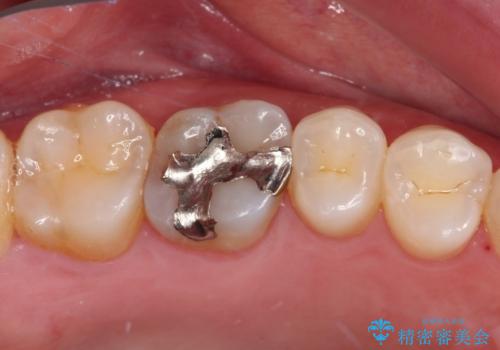

まず麻酔をして銀歯を外し、むし歯を除去し、形を整えて型取りします。

そして次の来院時、セラミックインレーを装着し、噛み合わせなどの調整を行います。

インレーを装着するときは、唾液や血液による接着力の低下を避けるためにラバーダム防湿を行いました。